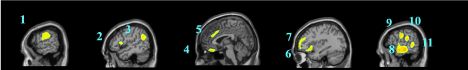

Figure 1C.  Sagittal slices showing the deficits of autistics subjects when compared to healthy controls using SPM (p < 0.001 FDR Correction). 1) Post and Precentral Right; 2) Right Triangularis; 3) Angular Gyrus Right; 4) Left inferior Orbital Cortex; 5) Cingulum Left; 6) Triangularis Left; 7) Frontal Cortex Mid and inferior Left); 8) Temporal Inferior Anterior Cortex left; 9) Precentral  Left; 10) Post Central Left;  11) Occipital Left.